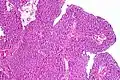

| Histopathology of transitional carcinoma of the urinary bladder. Transurethral biopsy. Hematoxylin and eosin stain. | |

Transitional cell carcinoma, being low-grade to the left, and high-grade to the right. H&E stain -

Papillary transitional cell carcinoma, low grade -